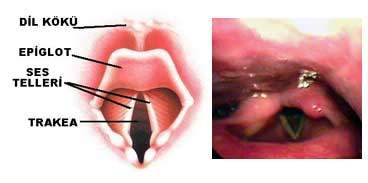

Gırtlak bölgesi aşaması

Endoskopi aleti dilin üzerinden ilerletilir ve önce orofarenks ve epiglottis bölgesi görüntülenir. Bu aşamada ağzın arka boşluğu, burundan gelen nefes yolu, ses telleri (cord vocalis), larniks, farinks görüntülenir. Tam bu aşamada hastadan tükürüğünü yutması istenir ve nefes borusunun hemen arkasından yemek borusuna (özofagus) girilir. Yutma refleksi nefes borusunu kapatırken yemek borusun açılmasını sağlar.